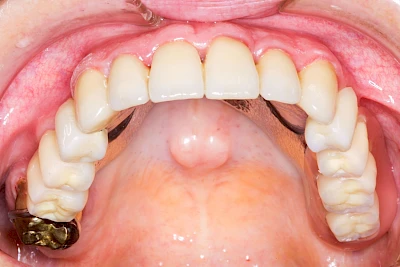

Überbeine im Bereich der Kiefer sind gar nicht so selten. Häufiger im Bereich der Seitenzähne unterhalb des Zahnfleisches, aber auch in der Mitte vom Gaumen. Überbeine haben in dem Sinne keinen Krankheitswert, müssen also nicht operativ entfernt werden, wenn diese nicht stören. Überbeine können ein Anzeichen für Knirschen und Pressen sein.